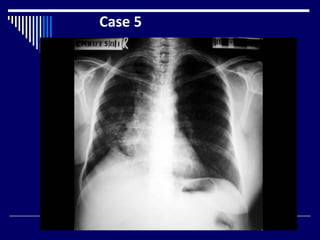

Case 5

Findings

• CXR

• Adult female (1)

• Right mastectomy (2)

• Tenting of right hemi diaphragm (1)

• Heterogeneous opacities right lower zone (1)

• Ipsilateral cardiac shift(1)

• Dx= CA right breast ( mastectomy ) with

radiation fibrosis (4)

Findings • CXR • Adultfemale (1) • Right mastectomy (2) • Tenting of right hemi diaphragm (1) • Heterogeneous opacities right lower zone (1) • Ipsilateral cardiac shift(1) • Dx= CA right breast ( mastectomy ) with radiation fibrosis (4)